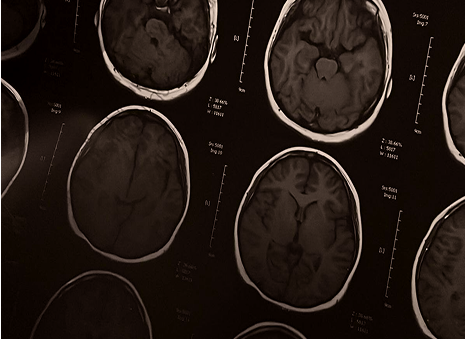

Seeing the body clearly, at the level of organs and systems.

Advanced medical imaging including MRI, CT coronary

calcium scoring, DEXA, and ultrasound